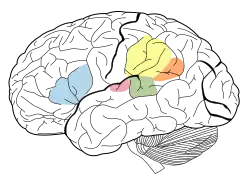

Giro angular

Giro angular é uma região do cérebro envolvida em inúmeros processos relacionados a linguagem, processamento de números, cognição espacial, resgate de memórias, atenção e a teoria da mente. Estimulação nessa área pode causar uma impressão de que se está fora do próprio corpo, aparentando ser uma viagem astral.[2]